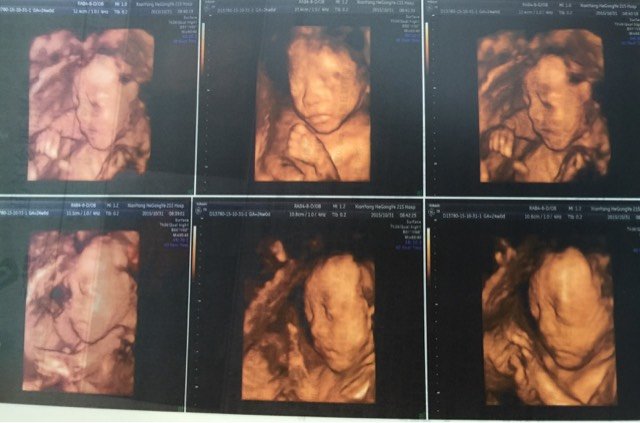

大家帮忙看看这是男宝宝还是女宝宝?有朋友说第三张那个是带把的也有说那是脐带,懂得人帮看看哦 大家帮忙看看这是男宝宝还是女宝宝?有朋友说第三张那个是带把的也有说那是脐带,懂得人帮看看哦 点击展开 137*****225_xqRM 2015-11-18 22:24 为您推荐: 其他回答 不会看,,, 锁心_ryds 2015-11-18 23:02 很明显那里是肚子所以是脐带。 CandyLady的轩宝 2015-11-18 23:00 不懂,,,, ^O^魔妈^O^ 2015-11-18 22:52 像脐带,宝宝张的像男宝 我亲爱的宝贝! 2015-11-18 22:49 感觉是男宝宝,恭喜 点点宝宝贝贝 2015-11-18 22:45 加载更多 相关问题 亲们有没有懂得,能看出来男宝宝还是女宝宝吗?还有脐带绕颈怎么办? 懂得宝妈们看看宝宝多少斤,脐带绕颈两周能顺产吗 懂得宝妈们看看宝宝多少斤,脐带绕颈两周能顺产吗